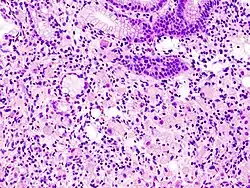

В гистологии перстневидными клетками называют клетки с большой вакуолью. Перстневидные клетки являются злокачественными и, как правило, обнаруживаются в карциномах. Перстневидные клетки наиболее часто выявляются при раке желудка, однако могут возникать в любом типе тканей, включая простату, мочевой пузырь, жёлчный пузырь, молочные железы, толстый кишечник, строму яичников и тестикулы.